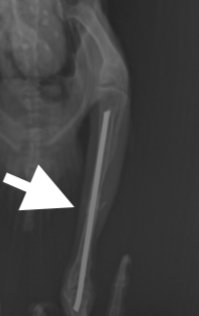

レントゲンを撮影すると頸足根骨がほぼ中央で骨折していることがわかりました。

骨折の部位、経過時間、本人の状態も手術可能な状態でしたので、ピンニング術を行うことにしました。

骨折部位の皮膚を最小限切開し、骨折部位を露出し、まずは遠位端(趾の方)にピンを挿入し、踵部の関節までピンを貫通させます。その後近位端にピンを挿入し、膝の関節は貫通しないように、長さを確認しながら、ピンを調節します。

最後に踵部から出ているピンを折り曲げ、適切な長さにカットし、テーピングをして手術は終了です。

約3週間経過したところで、骨の状態をレントゲンで再チェックし、仮骨形成を確認した後、ピンを抜く処置をしました。ピンを抜いた直後もしっかり足を動かしてました。